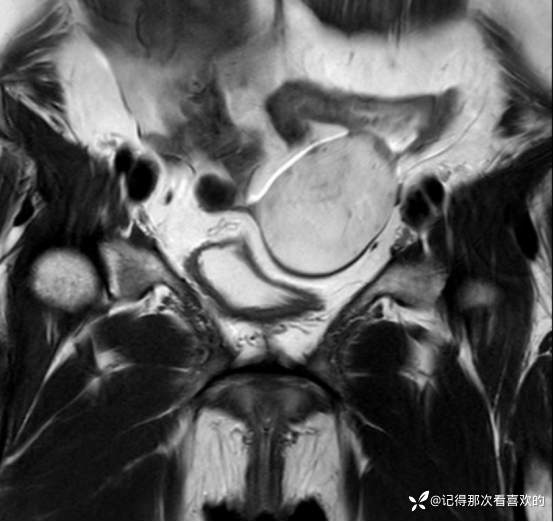

入院后查十二通道常规心电图:1、窦性心律2、逆钟向转位。余相关检验未见明显异常。于2025.05.30在静脉麻醉下行“宫腔镜诊断性刮宫术”,术顺,术后病理(2508387):(宫内容物)子宫内膜息肉。查心脏彩超(Z250530002):三尖瓣轻度反流。双侧下肢深静脉血管彩色多普勒超声(Z250530003):双侧下肢股总静脉反流,考虑双侧下肢深静脉瓣功能不全。经阴道彩超检查(Z250530004):双侧附件区低回声不均团块,考虑MT,建议进一步检查。子宫多发肌瘤。子宫内膜区低回声结节,考虑粘膜下肌瘤可能。宫颈腺体多发囊肿。盆腔MRI增强(MR109286):1.双侧附件区团块状占位,考虑MT,请结合临床。2.子宫肌层内、浆膜下多发肌瘤。3.子宫腔内异常结节灶,粘膜下肌瘤可能。4.盆腔少量积液。5.右侧髂骨内结节灶,性质待定,建议进一步检查。胸部CT(CT384707):1.双肺多发微小结节,建议随诊复查。2.气管憩室。3.扫及右肾结石?新上腹部CT平扫(CT384838):盆腔右侧占位性病变,请结合临床及MRI检查。HPV+TCT:HPV阴性;非典型鳞状上皮细胞(不能明确意义)。2025.06.03行胃肠镜,电子胃十二指肠镜检查(PG25003031):胃体溃疡(待病理);慢性萎缩性胃炎。电子结肠镜检查(PC25002608):结肠多发息肉(内镜下息肉切除+钳除)。快速石蜡病理(2508504):胃体:低分化腺癌,伴少量印戒细胞癌成分,免疫组化结果待补充报告。快速石蜡病理(2508505):降结肠:增生性息肉。